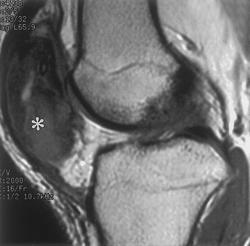

Гигантоклеточная опухоль.

Злокачественная гигантоклеточная  опухоль возникает из доброкачественной (частота 10-20%). После операции возможно появление рецидива опухоли.